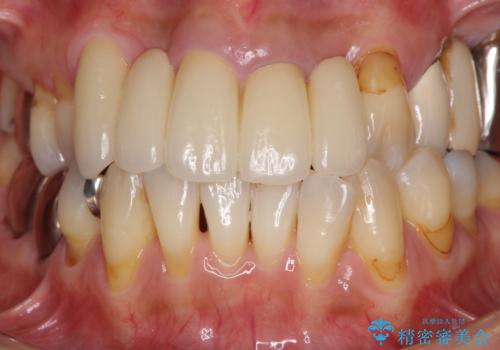

露出していた歯根や金属の縁が見えてしまい、なかなか口を開けて笑うことができなかったのですが、歯肉の位置に縁を合わせることで自然な仕上がりとなりました。

ブリッジの隙間にものが詰まったり、空気が抜けたりすることも無くなり、話しやすさも改善することができました。

露出していた歯根が覆われるため、歯冠が長く見えてしまうことが懸念されましたが特に気になることはなく、患者様には大変満足していただきました。